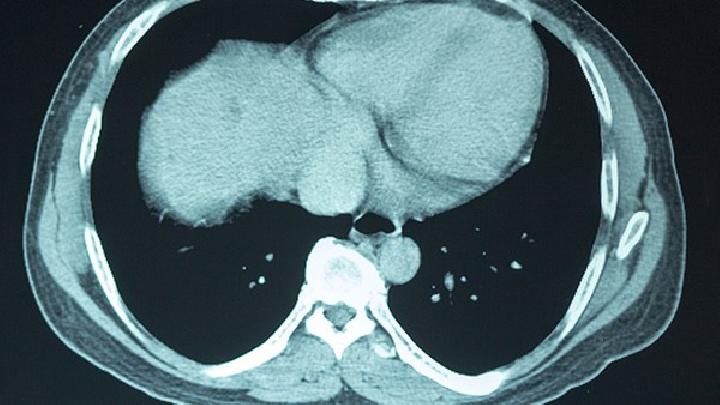

“血管炎”确切地说,应该称为“系统性血管炎”。之所以冠以“系统”二字,是因为血管炎可以累及到人体的各个系统。其实也容易理解,血管无处不在,病变自然也可以多部位发生了。常见累及的器官及表现有:肺部:出现弥漫性、间质性或结节性病变,可以有咳嗽、气急、呼吸困难等表现;肾:出现血尿、蛋白尿,发生率高,常较早出现肾功能减退;肝脏:出现肝区不适、肝功能损害;心血管:出现无脉、双侧肢体血压差异增大。神经系统:因向颅内供血血管病变,引起脑缺血的症状、颅内血管炎可引起颅内出血或结节样病灶。